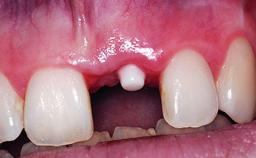

A healthy 28-year-old female patient presented for a consultation on treatment options to restore her upper right central incisor. At the clinical examination, the tooth responded to percussion and palpation. The gingiva was red and slightly swollen, with a mid-facial probing depth of 10 mm. The upper right lateral incisor showed no signs or symptoms, did not respond to exploration and percussion, and the vitality test was positive. The periapical radiograph revealed that tooth 11 had been endodontically treated, with no lesion evident at the apex. A small radiopaque calcified structure surrounded by a narrow radiolucent zone (3 × 3 mm) was present at the apex of tooth 12.